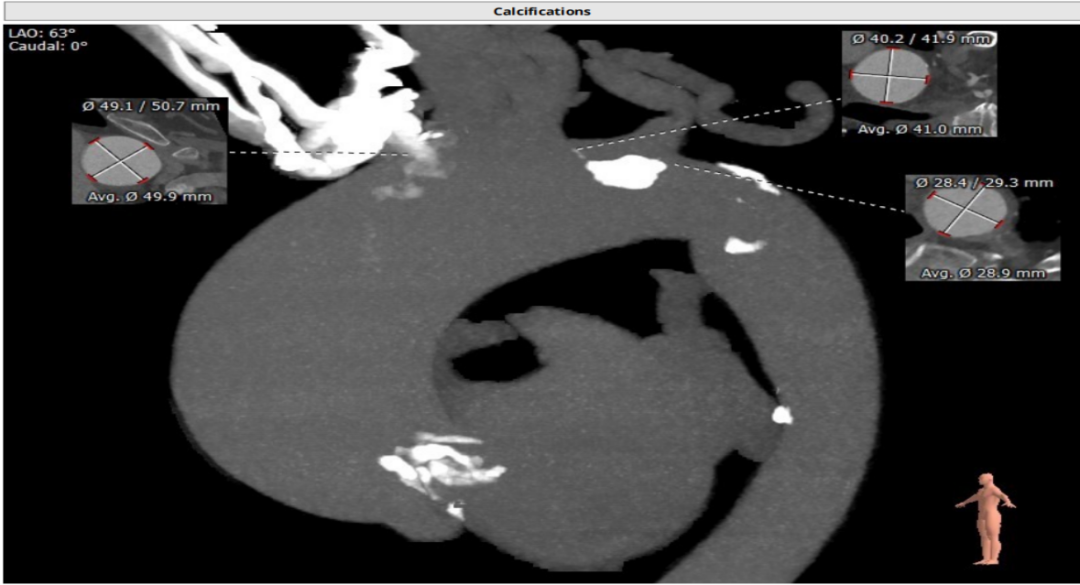

老年女性;主诉:活动后胸闷3年余。超声心动图显示:主动脉瓣狭窄(重度)并少中量反流,主动脉瓣二瓣化畸形,主动脉最大流速4.8m/s,平均PG 70mmHG。CT影像显示:主动脉瓣中度钙化,主动脉瓣环内径24.4mm,LVOT 26.8mm,STJ 36.4mm,升主动脉增宽50mm,横位心角度75°。

团队讨论后认为,病人主动脉钙化较为严重,特别是无名动脉钙化更为严重,存在横位心的跨瓣难度以及球扩后钙化脱落风险,因此选择在脑保护装置的辅助下完成TAVR手术。